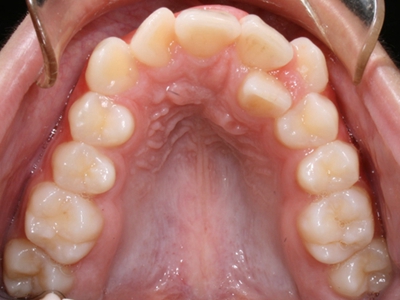

阻生牙是指由于邻牙、骨或软组织的阻碍而只能部分萌出或完全不能萌出,且以后也不能萌出的牙。引起牙阻生的成因,主要是由于颌骨缺乏足够的空间容纳全部恒牙。常见的阻生牙为下颌第三磨牙、上颌第三磨牙及上颌尖牙。

阻生牙主要原因是随着人类的进化,颌骨的退化与牙量的退化不一致,导致骨量相对小于牙量,颌骨缺乏足够的空间容纳全部恒牙。

发育正常的牙齿同时正畸治疗又不需要进行拔牙矫治,通常需要对阻生牙进行牵引治疗,引导进入牙弓,而对于发育异常的阻生牙加之正畸治疗需要进行拔牙矫治,通常可以考虑将阻生牙拔除,而避免再拔发育正常的前磨牙,即降低了正畸治疗的难度及不确定性,又保留了相对正常的牙齿。